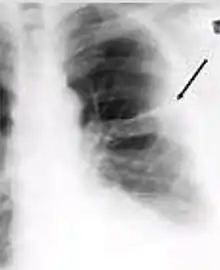

Chest X-ray of a person with advanced tuberculosis: Infection in both lungs is marked by white arrow-heads, and the formation of a cavity is marked by black arrows.